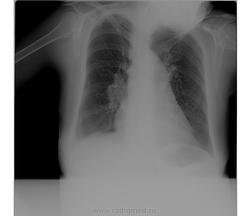

Для начала ее бы ровно снять... Лимфаденопатия правого корня, что там с левым не очень ясно. Туб. бронхоаденит маловероятен в силу возраста. Над всем остальным пусть клиницисты думают

Кахексия, остеопороз с гиперкифозом. По неправильной установке и странной позе - энцефалопатия(?)))). Для 46 многовато, вот и переспросил)). +1 к снимку в стандартной укладке.

За туберкулёз данных нет.Лимфоаденопати в таком возрасте маловероятна.Норму не напишешь.Остаётся "наиболее вероятна картина саркоидоза".И обязательно-"при неудовлетворительной установке объекта".

Вы тогда все свои сомения аккуратно опишите (ни на чём не настаивая) и порекомендуйте повторить сником при правильной укладке.Может быть справа корень расширен, за счёт сосудистой тени, вообще у пациентки магистральный тип сосудов ( широкие, маловетящиеся).

Написал бы то, что видно: Р-признаки эмфиземы легких (диафрагма опущена, уплощена, наличие легочной "талии"), артериальной гипертензии в малом круге кровобращения (выбухает 2 дуга по левому контуру сердечной тени, корни расширены за счет сосудов); "метелка" в области головки левого корня провоцирует размышления на тему центрального рака. Ну, и еще раз уточнил бы паспортные данные, не похоже на 46 лет (ксерокс паспорта или полиса ОМС обычно лежит в кармашке истории болезни).

Кифосколиотическая деформация грудной клетки; легочная гипертензия. Возможно, переснять "ровнее" не удастся. Думаю, скиалогический возраст пациентки и неправильную укладку можно объяснить деформацией грудной клетки, как минимум, "с юности". Группа инвалидности по бронхиальной астме тоже с юности? Знание анамнеза помогло бы уточниться с анализом рентгеновского архива.

Андрей Юрьевич, добрый вечер! имхо: выбухание 2 дуги по левому контуру сердца, скорее всего из-за установки при съёмке. Может быть и не стоит говорить об эмфиземе лёгих т.к.нет расширения ретростернального пространства (а, "лёгочная талия" вероятно отять же, за счёт укладки (поворот).О лёгочной гипретезии можно достоверно говорить , только после проведения эхокардиографии, по признаку разницы градиентов давления в лёгочной артерии.

Написал бы то, что видно: Р-признаки эмфиземы легких (диафрагма опущена, уплощена, наличие легочной "талии"), артериальной гипертензии в малом круге кровобращения (выбухает 2 дуга по левому контуру сердечной тени, корни расширены за счет сосудов); "метелка" в области головки левого корня провоцирует размышления на тему центрального рака.

Увеличение лимфоузлов я бы со счетов не сбрасывала - вид у корня не "сосудистый", сегментарные сосуды совсем не расширены

Так и есть, симптом "скачка калибра".

Я бы сделала томографию средостения чтоб исключить или подтвердить увеличение л.у,центральный рак.

Нужен архив, сердечный анамнез (порок?), правосторонняя лимфаденопатия, вероятнее, сосудистого характера?